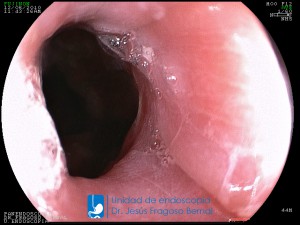

La Unidad de Endoscopía fue creada en 2002 por el Dr. Jesús Fragoso Bernal, es pionera en el estado por la utilización de la tecnología más avanzada, que nos permite ofrecer servicios integrales de diagnóstico y tratamiento para las enfermedades del aparato digestivo.